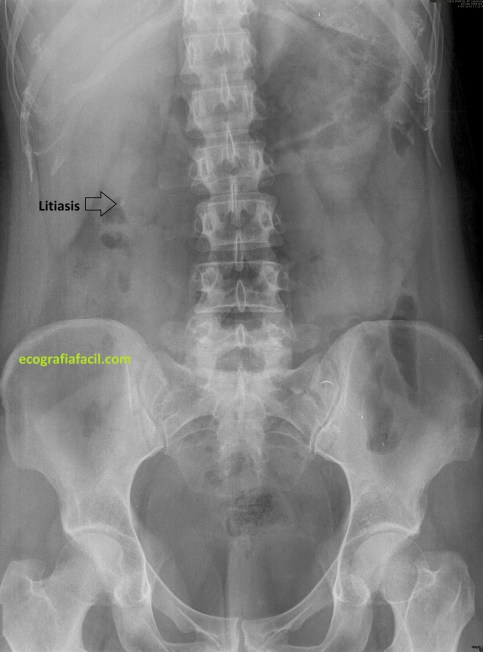

Realizar Rx de Abdomen a la búsqueda de litiasis renales es normal, sobre todo en los servicios de urgencia de los hospitales, con el fin de demostrar la causa ante una sospecha de cólico nefrítico. el uso del TC es más restringido, sólo a casos donde la litiasis no se vea con la la Rx y tampoco con una eventual ecografía de urgencias y la sospecha pueda ser como primera opción, un CRU.

La secuencia de imágenes que has visto es el proceso que ha llevado la paciente, con una ecografía antes del TC con el mismo resultado en cuanto a litiasis que la última que corresponde con las imágenes 6, 7 y 8 donde puedes ver la litiasis renal derecha grande, en el grupo calicial inferior en longitudinal y en transverso. Riñón izquierdo rigurosamente normal, por más que pude buscar, aún a sabiendas de que en el TC habían salido piedras en ese riñón, además, agrupadas en los diferentes grupos caliciales, imágenes 2 y 5, en las reconstrucciones coronales como en los cortes axiales, pero llama poderosamente la atención como junto a la litiasis del RD en el TC, imagen 3, se ven otras dos pequeñas litiasis, imagen 4, que tampoco pude objetivar en la ecografía, ni se vieron en la ecografía anterior. La Rx señala la vista en las ecografías.